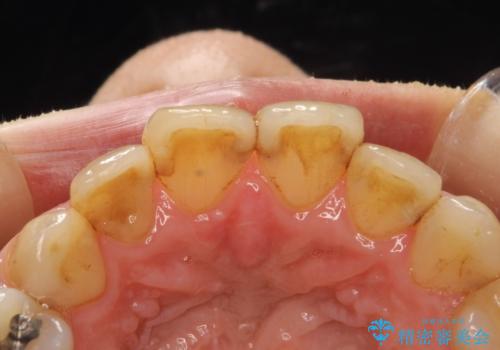

歯と歯の間の着色除去

- 着色が歯と歯の間や、詰め物との境目に多い患者様。

細かい部分まで届くようにエアフローにて施術しました。

詰め物との境目の汚れは、ポリッシングブラシでは取り除くことが難しいため

エアフローの細かいパウダーを角度を変えて当ててとれる範囲で除去しました。